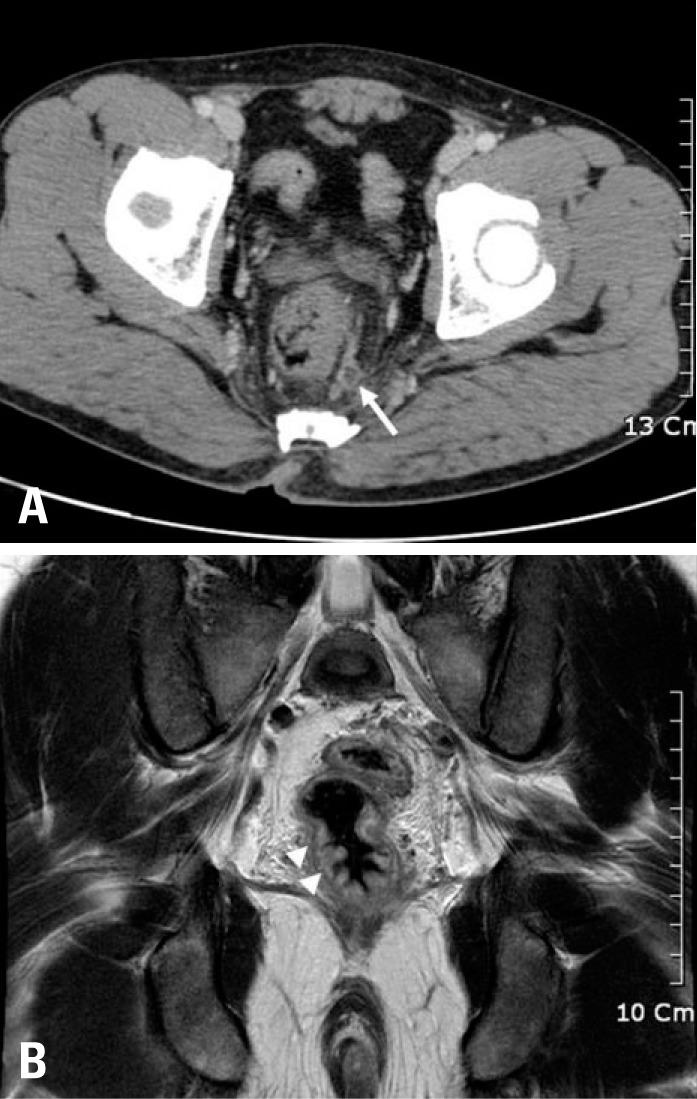

Rectal syphilis, known as a great masquerader, can be difficult to diagnose because of its variable symptoms. Gastroenterologists should be aware of the possibility of rectal syphilis when confronted with anorectal ulcers, and should gather a detailed history about sexual preferences and practices, including homosexuality. We report a case of primary rectal syphilis mimicking rectal cancer on radiologic imaging. In this report, we described the clinical, endoscopic, and radiologic features of this rare case.